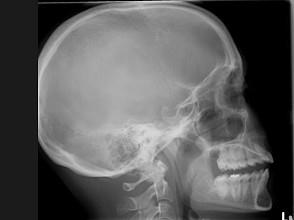

问题 25岁女性,车祸伤及面部,X线及CT检查如图所示,下列哪些描述或诊断正确 ( )

选项 A、考虑为左侧眶底骨折 B、左侧上颌窦积液 C、CT发现左侧眶底骨质断裂 D、左侧上颌窦内见气-液面 E、X线示左侧眶底较正常变低

答案 ABCDE